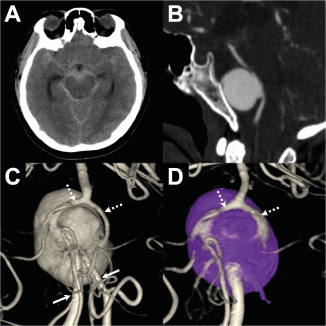

A 63-year-old female presented in the emergency department with severe vomiting and acute consciousness change (Hunt and Hess score of 3). Non-contrast computed tomography (CT) revealed Fisher grade 4 diffused subarachnoid hemorrhage and an associated hydrocephalus (Figure 1A). A subsequent CT angiography revealed an anteriorly directed 26 mm sized giant saccular aneurysm at the vertebrobasilar system (Figure 1B).

Figure 1. Extensive diffuse subarachnoid hemorrhage is seen over the basal cisterns and hydrocephalus in brain computed tomography (CT) (A). The sagittal view of the CT angiography shows an anterior directing giant saccular aneurysm at the vertebra-basilar system (B). Pre- (C) and post-treatment (D) posterior views of the three-dimensional rotational angiography with volume rendering were obtained from the left vertebral artery (VA) injection. Before treatment, the giant aneurysm is associated with two VA inlets (sold arrows) and two basilar fenestration outlet limbs (broken arrows) (C). Following endovascular treatment, the vertebra-basilar arterial system is reconstructed with a stent deployed from one side of the VA, across the aneurysm, toward the ipsilateral fenestration limb. The aneurysm is completely secured by dense aneurysm coil packing closing-off all possible inflow. Notice that the un-stented basilar fenestration limb is well opacified from the stented fenestration limb (broken arrows) (D)

The patient was promptly intubated, and the acute hydrocephalus was managed with an external ventricular drainage. Cerebral angiogram was then performed to delineate the detailed aneurysm morphology. Volume rendering from the three-dimensional rotational angiography of the right VA injection revealed that the giant aneurysm was associated with two inlets and two outlets (Figure 1C). The two inlets were co-dominant in size and converged into the aneurysm pouch. The posterior inferior cerebellar artery arose from each inlet limb, indicating that the two inlets represented the VAs. The two outlets, which came out from the aneurysm dome and gave off anterior inferior cerebellar artery from their proximal segments, joined distally into a single BA, indicating that each outlet limb represented a fenestration limb of the unfused lower BA (Figure 1).

Dual antiplatelet medications (300 mg aspirin and 300 mg clopidogrel) were administered before the procedure. The endovascular procedure was performed through the bilateral vertebral routes after placing a 6-Fr Envoy® guiding catheter (Codman Neurosurgery, Raynham, Massachusetts, USA) in each distal V2 segment. A Headway™ 21 microcatheter (Microvention-Terumo, Tustin, California, USA) was advanced in the left VA, across the aneurysm, and finally reaching the left outlet fenestration limb. A 4.0 x 22 mm LVIS™ stent (Microvention-Terumo, Tustin, California, USA) was then back-loaded and deployed from the left basilar fenestration limb to the left VA. An Excelsior™ SL-10 microcatheter (Stryker Neurovascular, Kalamazoo, MI, USA) was then advanced in the right VA and placed within the aneurysm dome. A total of 49 Target® coils (Stryker Neurovascular, Kalamazoo, MI, USA) were deployed to secure the aneurysm. A final angiogram showed complete occlusion of the aneurysm, while both fenestration limbs and all cerebellar arteries remained patent. (Figure 1D) There were no procedure-related complications. No ischemic events were observed in post-procedural brain magnetic resonance imaging (MRI). The patient achieved good outcomes, with a modified Rankin scale of 0 at 3 months. A control angiogram at the 6-month follow-up revealed no aneurysm recanalization.